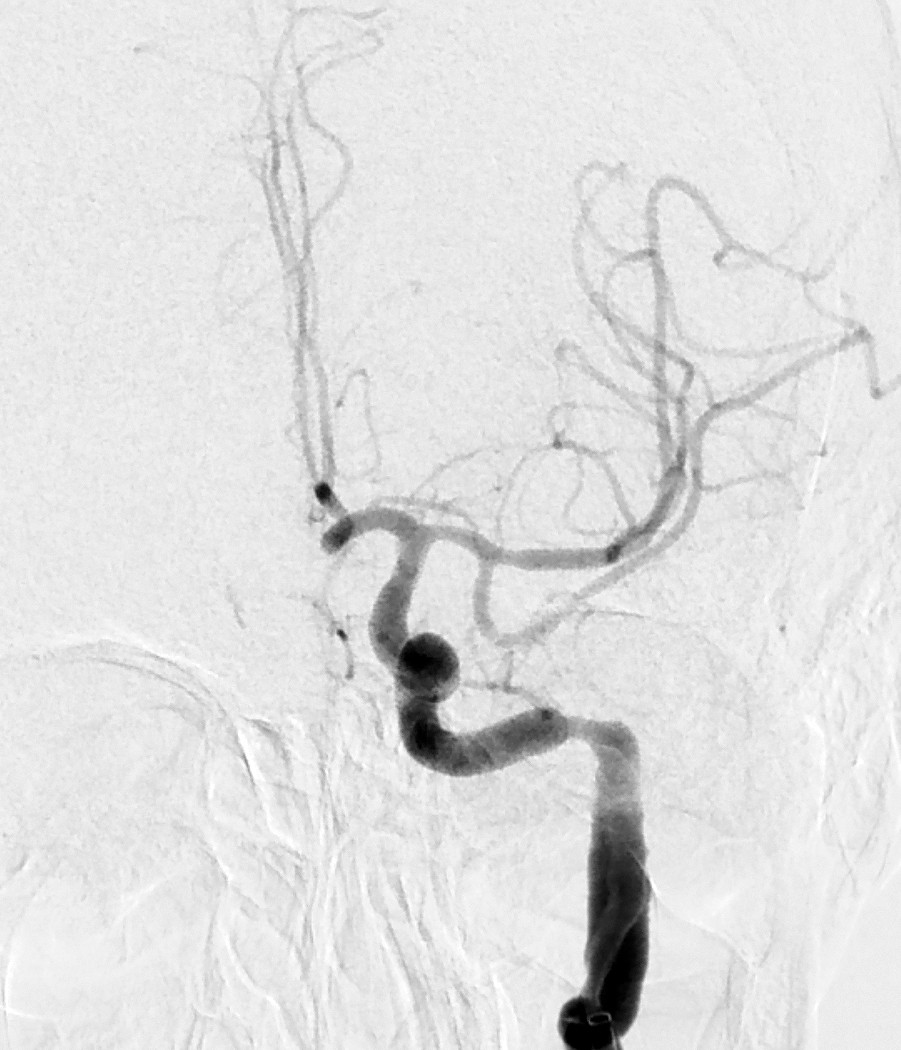

Myren-Svelstad S, Hammer TA, Idicula TT. Early thrombectomy of a proximal middle cerebral artery occlusion leading to complete recovery with no infarct. Case Rep Neurol 2017; 9: 76 - 80. [PubMed][CrossRef]

Vi vil takke for en fin kasuistikk som til fulle viser hvilket potensiale mekanisk rekanalisering (trombektomi) har ved cerebral storarterieokklusjon. Antall som må behandles for én pasient skal komme gjennom et hjerneinfarkt med mindre grad av funksjonshemming (Number Needed to Treat, NNT), er 2,6. I Norge gjennomføres trombektomi per dags dato ved fem sykehus, og to nye sykehus skal starte med trombektomi fra neste år.

De fem store randomiserte trombektomi-studiene inkluderte hovedsakelig pasienter med større nevrologiske utfall. De fleste studiene hadde NIHSS-skår på minst 6 som nedre grense mens MR CLEAN-studien inkluderte pasienter med NIHSS-skår på minst 2 (1). Etter publiseringen av disse studiene er det blitt rutine å trombektomere pasienter også med lettere utfall. I metaanalysene hadde 581 pasienter NIHSS-skår < 8 og 413 pasienter NIHSS-skår ≤ 5. De som ble behandlet med trombektomi, hadde signifikant bedre funksjonsnivå etter 3 måneder sammenliknet med dem som kun fikk medisinsk behandling (2, 3).

Ved St. Olavs Hospital synes man å ha en meget konservativ utvelgelse av pasienter for trombektomi. Forfatterne skriver at behandlingen vanligvis ikke gjøres ved NIHSS-skår < 10. Vi mener i overenstemmelse med publiserte metaanalyser at en slik høy grense for intervensjon gjør at endel pasienter går glipp av svært viktig akuttbehandling. Målet med trombektomi er å begrense skadevolumet i hjernen, ikke å reperfundere et hjernevolum som allerede er nekrotisk. Ved de andre trombektomi-sentrene i Norge vektlegges derfor CT/MR penumbra-vurdering, kollateralsirkulasjon og eventuelt diffusjonsfunn på MR sterkere enn selve NIHSS-skåren når indikasjonen for trombektomi stilles. I OUS-materialet fra 2017 hadde 39 av totalt 120 pasienter (32,5 %) NIHSS-skår < 10 på indikasjonstidspunktet (abstrakt presentert på Nevrodagene 2018 ved B. Enriques og medforfattere). Disse hadde klinisk og radiologisk et stort truet penumbravolum. Ved å bruke høy NIHSS-skår som indikasjon og ikke en individuell fysiologisk tilnærming vil trolig for få pasienter bli behandlet og det samlete resultatet etter trombektomi bli vesentlig dårligere enn det kunne ha vært.

Vi takker Anne Hege Aamodt og medarbeidere for en hyggelig og viktig kommentar. Beklageligvis ligger pasientkasuistikken noe tilbake i tid, utarbeidelse av manuskript likeså. I Trondheim benyttes CT/MR for vurdering av penumbra og kollateralsirkulasjonen vektlegges. At NIHSS-skår ikke kan benyttes som indikasjon alene er selvsagt, og denne misforståelsen beklager vi. Samtidig bør det være et visst nevrologisk utfall før en invasiv prosedyre utføres. Ved St. Olavs hospital gjøres i dag normalt ikke trombektomi ved NIHSS-skår ≤ 5, men alle pasienter som kan være kandidat til trombektomi, får en individuell vurdering, også de med lavere NIHSS-skår.